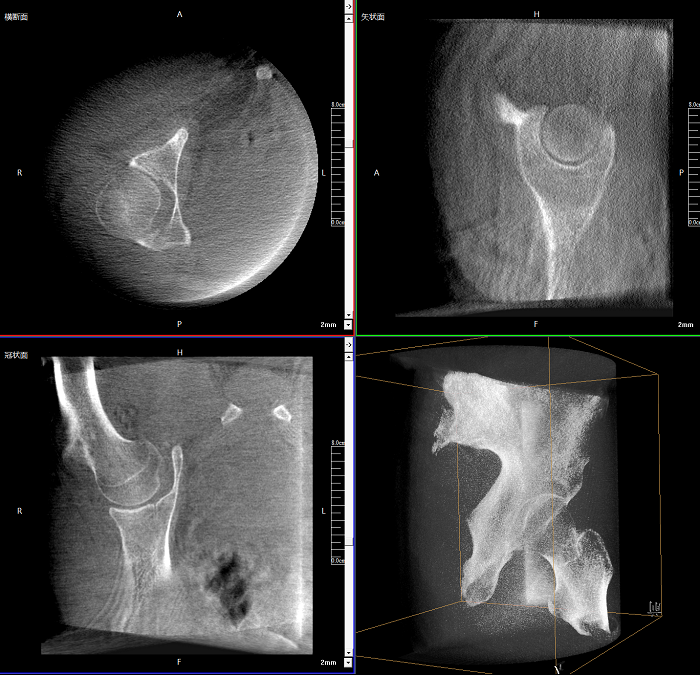

三維成像 全面觀察

任意視角、任意切面觀察

術(shù)中實(shí)時(shí)生成橫斷面、矢狀面、冠狀面及三維影像,可在任意切面、任意角度評(píng)估植入物和解剖結(jié)構(gòu)的相對(duì)位置。

Clinical picture

臨床圖片